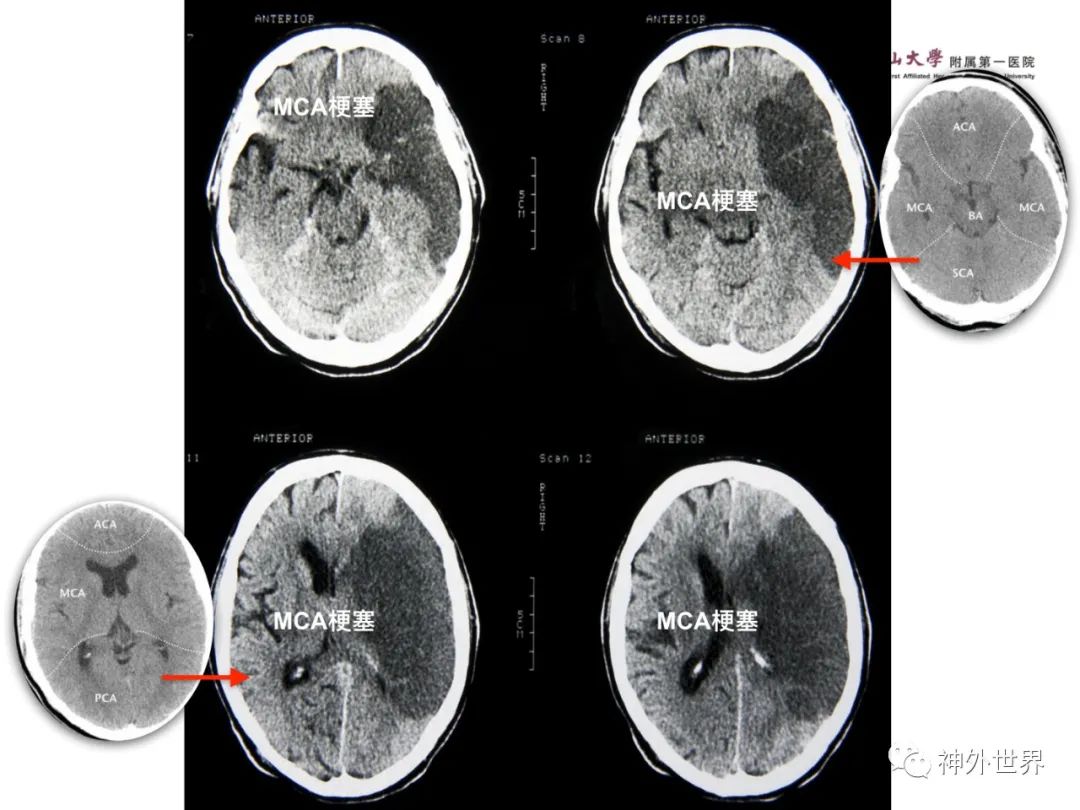

大脑MR、CT 的阅片技巧,超赞 !